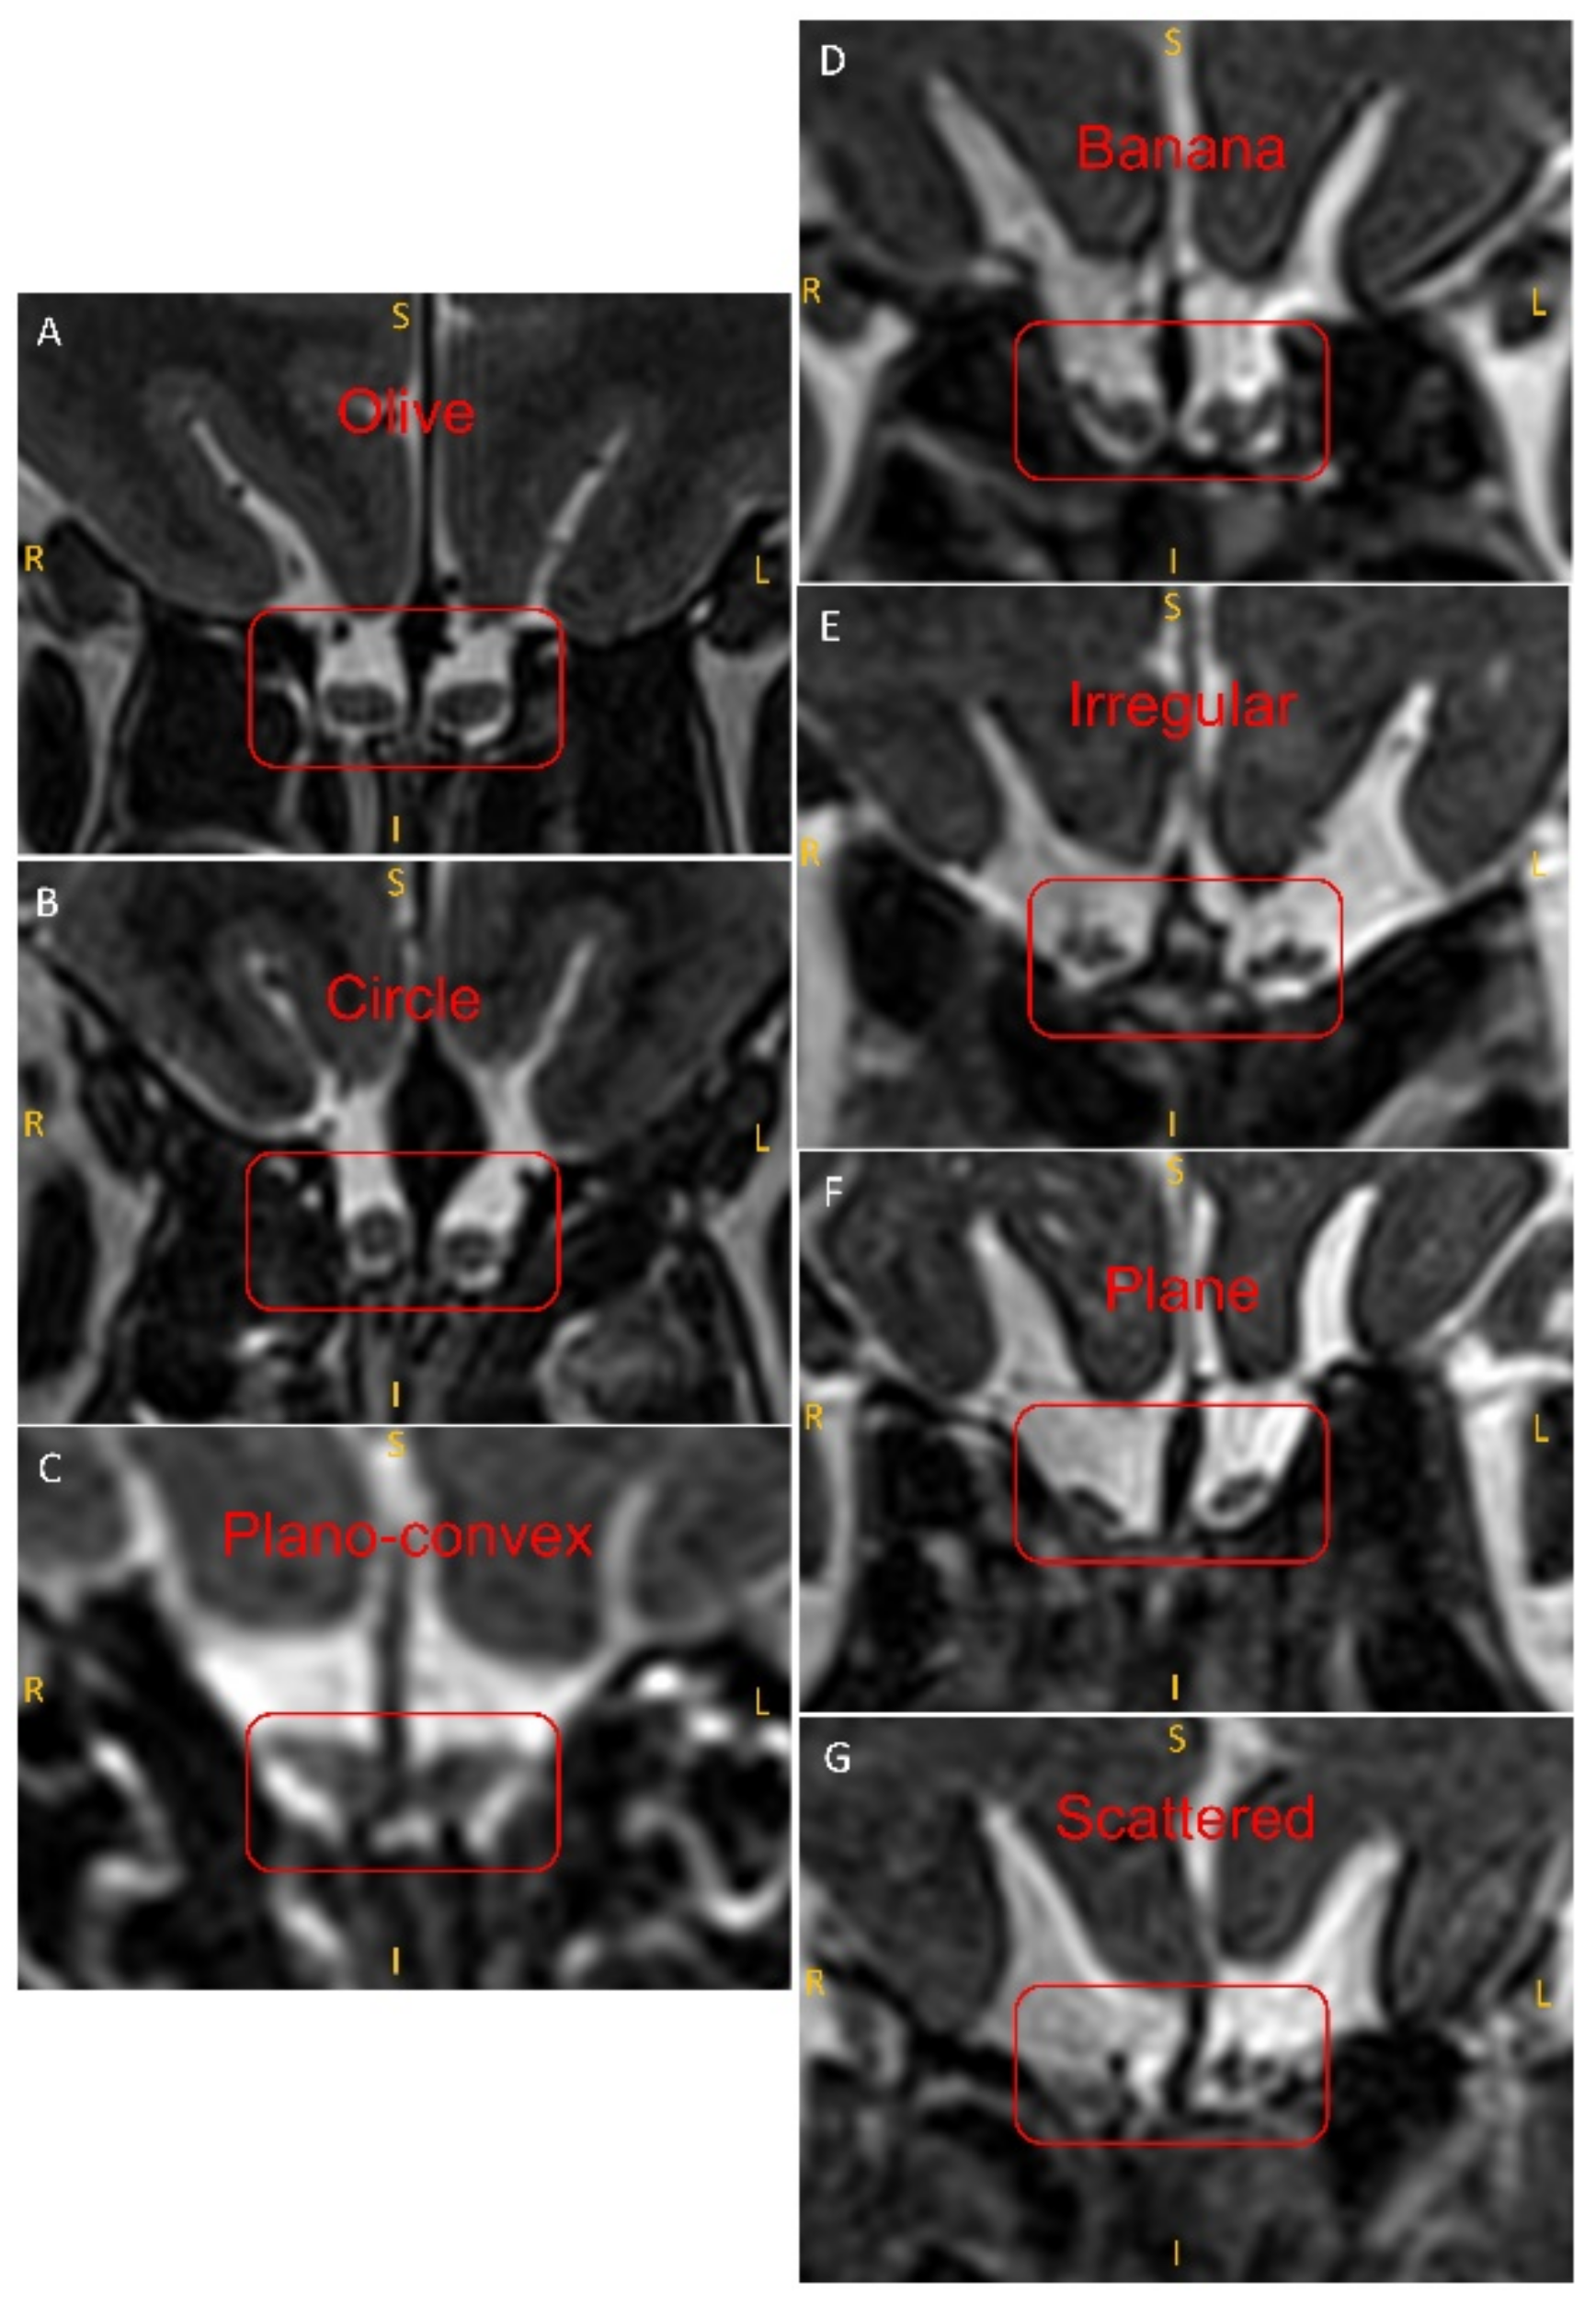

2.4. Evaluation of the Shape of the OB

3.2. Comparison of Patients and Controls in Terms of OB Shapes

3.3. Correlation of OB Shapes with the Olfactory Function